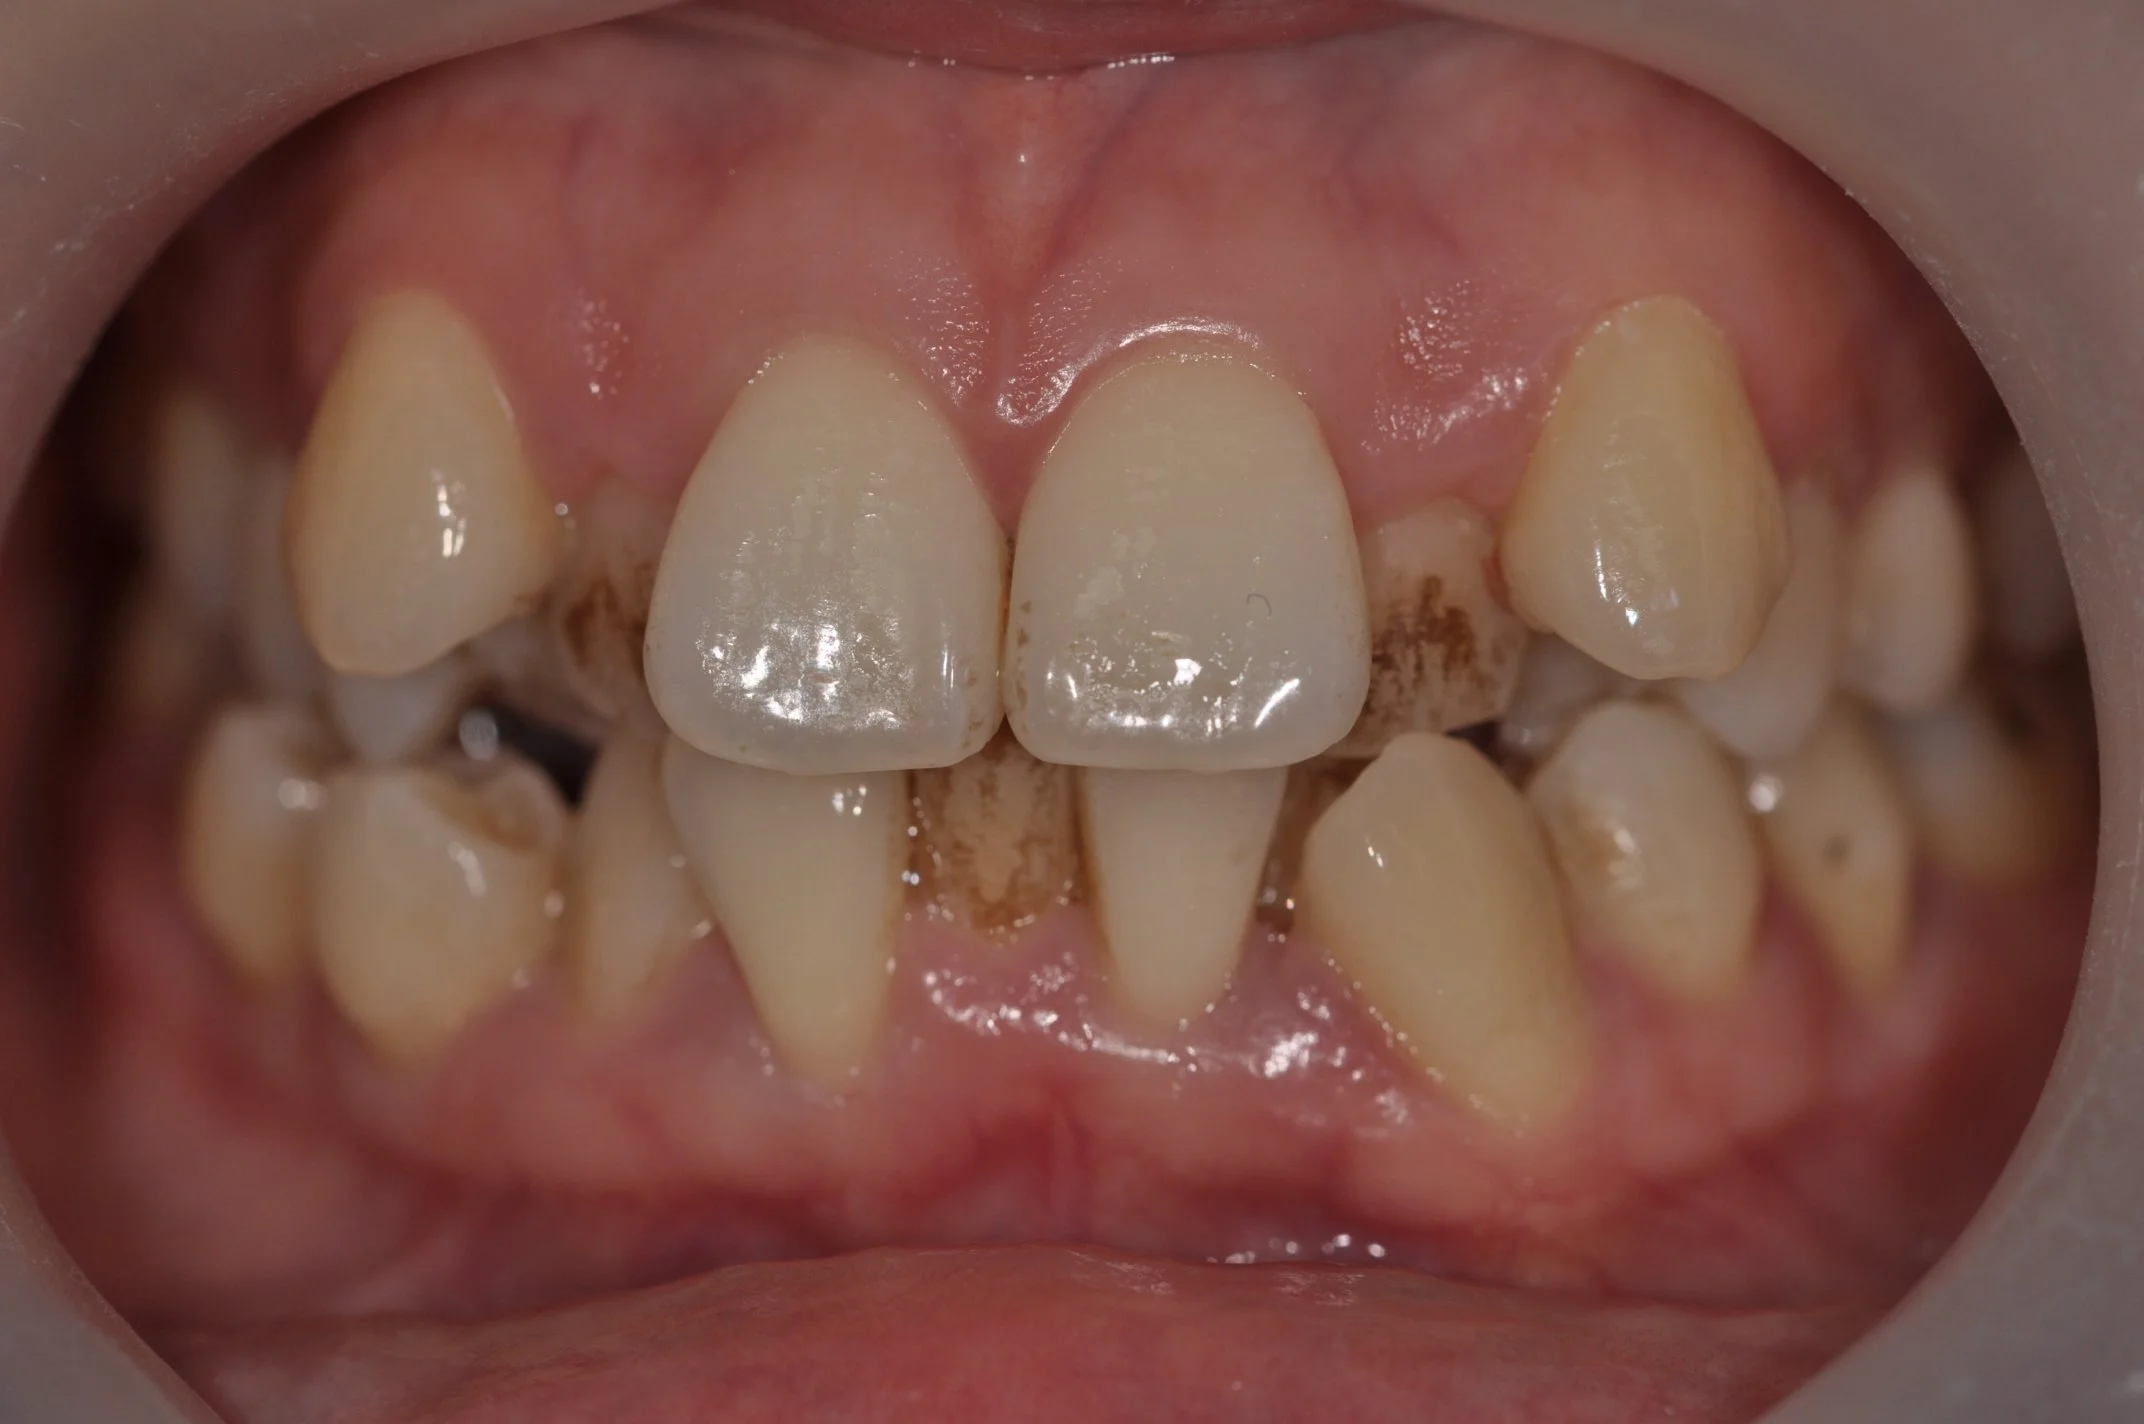

Jason Hp PA Preop.jpg

Failing Natural Central Incisor

(Upper front tooth)

Jason Ho Issue implant-crown.jpg

Replacement with a dental implant and full ceramic crown